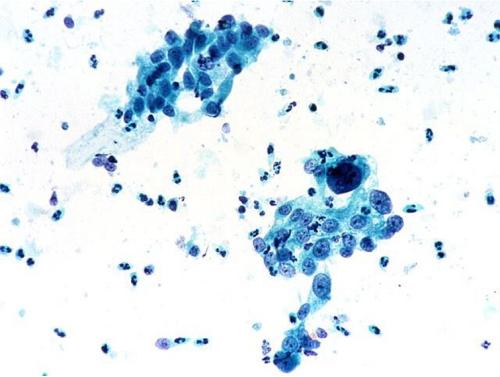

病毒往往會依賴宿主細胞進行復制,但病毒是如何誘導宿主轉錄自身的遺傳信息來制造病毒顆粒的呢?幾十年來,科學家們一直在研究一種名為λ(lambda)的噬菌體來試圖找到答案。

近日,一項刊登在國際雜志Molecular Cell上的研究報告中,來自柏林夏里特醫(yī)學院的科學家們利用高分辨率的冷凍電鏡技術成功解析了上述過程。

沒有宿主就沒有病毒,盡管病毒能通過宿主外環(huán)境來傳播擴散,但其仍需要宿主來進行繁殖,病毒缺少復雜的結構來將遺傳信息進行轉錄并轉化成為新的病毒顆粒,這也就是為何所有病毒都需要使用宿主細胞的分子結構的原因;長期以來,科學家們一直在研究病毒成功利用宿主細胞功能的機制,如今他們對細菌噬菌體進行了深入研究,噬菌體能依賴細菌宿主細胞來進行繁殖。

此前研究人員發(fā)現(xiàn),λ噬菌體能將自身的遺傳信息引入到宿主細胞中,并將其插入到宿主細胞基因組的特殊位點中;RNA聚合酶是一種負責轉錄遺傳信息的蛋白質復合體,其能在細菌基因的末端停止閱讀相關信息,并忽略所插入的病毒基因;λ噬菌體能利用一種特殊的技巧,抑制RNA聚合酶終止轉錄過程,其能引入lambda-N(λN),這是一種微小蛋白,其能吸附到宿主RNA聚合酶上并驅動RNA聚合酶對病毒的基因繼續(xù)轉錄;截止到目前為止,研究人員并不清楚λN是如何完成上述過程的,這項研究中,研究人員就利用高分辨率成像技術對RNA聚合酶-λN復合體的3-D結構進行了成像研究,這就能幫助他們清楚地解釋λN的作用原理。

研究人員分別制造出了大型蛋白復合體的各個組分,將這些組分組裝后,將其放入一層薄薄的水膜中并對其進行冷凍處理,利用冷凍電鏡技術,研究人員從不同角度對蛋白復合體進行了總共70萬張圖像的分析,隨后來計算其三維結構,這些結構的本質就告訴我們,小型的病毒λN蛋白能將RNA聚合酶的兩部分密封在一起,一旦其到達細菌基因末端的停止信號時就能抑制其發(fā)生分裂。

RNA聚合酶就能夠在抵達病毒基因時繼續(xù)轉錄,一旦所有的病毒基因被讀取完畢,病毒就能夠利用宿主細胞來制造子代病毒,研究結果解釋了科學家們長期的研究難點,相關研究發(fā)現(xiàn)有望幫助研究人員開發(fā)新型的抗菌藥物。